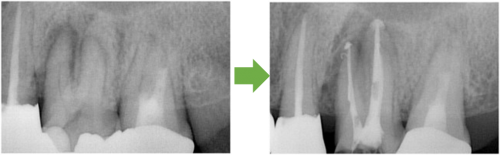

歯髄壊死 右上の前歯 川口の歯科 歯医者 さかえ歯科クリニック

2014年12月16日

術 前 術 後